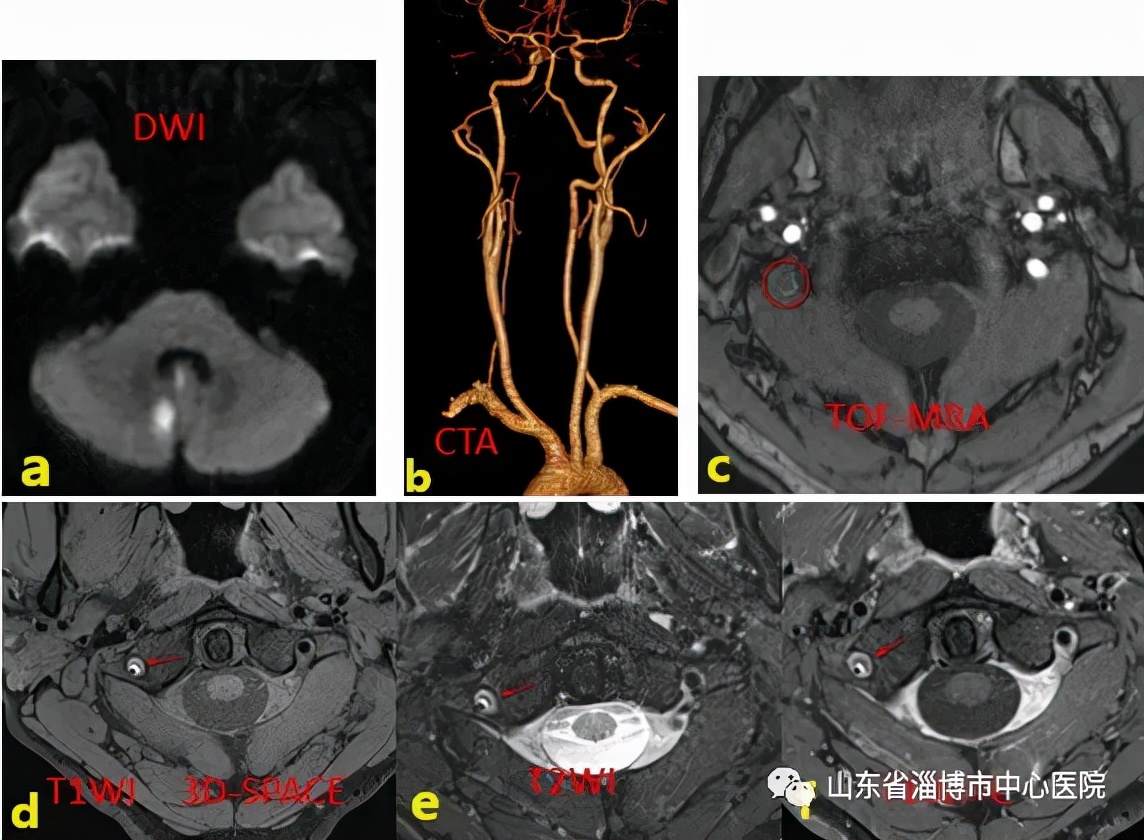

患者25岁,有颈椎按摩史,头晕头痛半天,入院诊断突发小脑梗死。

图示a:DWI序列示小脑新发脑梗死;b:头颈部CTA示右侧椎动脉远段未显影;c:MRA示右侧椎动脉远段未见显影;d:高分辨T1像显示双腔征;e:T2序列显示双腔征,内膜片;f:增强扫描假腔未见明显强化。综合诊断为右侧椎动脉夹层。